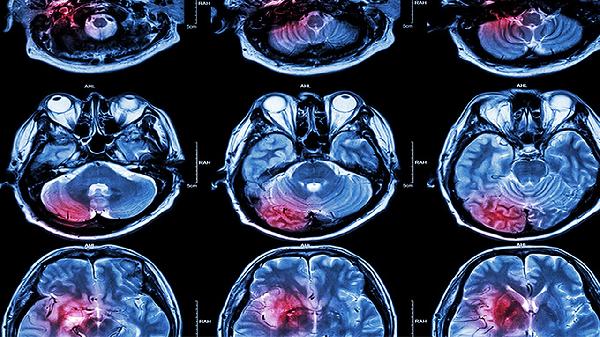

头部5种情况常出现,警惕脑溢血发出的信号!医生:该去做个检查了

早上起床突然眼前一黑,扶住墙才没摔倒;开会时半边脸莫名其妙发麻,还以为是空调吹的……这些看似普通的状况,可能藏着危险的蛛丝马迹。脑溢血这个听起来遥远的疾病,其实悄悄给身体打过不少"预警电话",只是我们常常错当成了"疲劳欠费通知"。